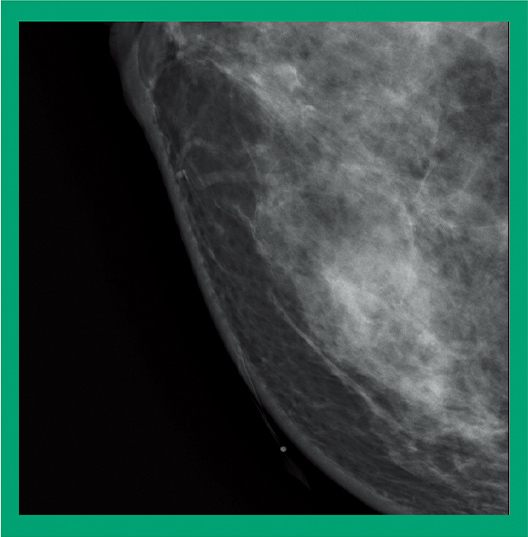

This function reduces the compression pressure within the range (± 3 mm) where the thickness of the breast does not change after the completion of normal breast compression and therefore reduces the pain of the patient. The hysteresis*1 phenomenon is used to reduce the time that the pressure is at maximum pressure compared to normal compression methods.

29kV 44mAs 0.83mGy

34mm 62.8N

- *1 Hysteresis: A phenomenon in which the state of a substance or system depends on the course of forces applied in the past.